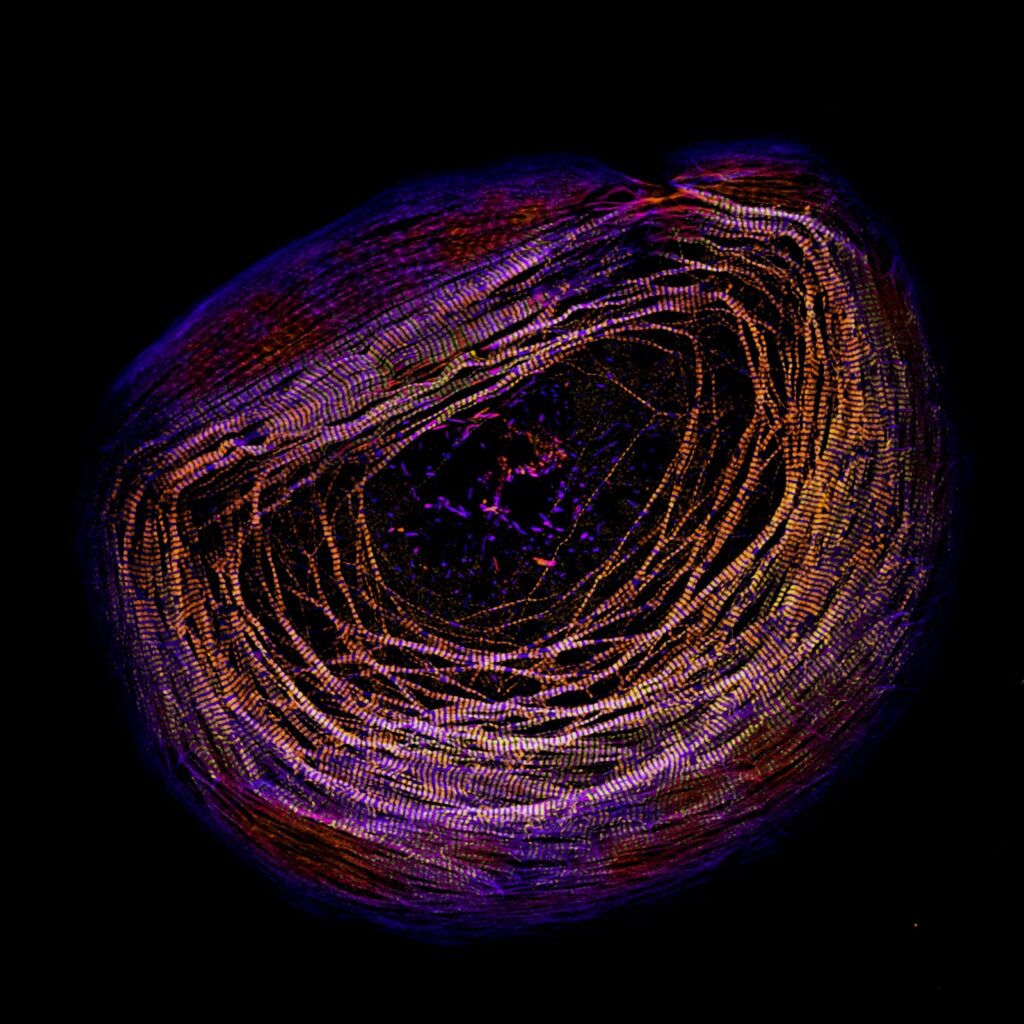

“We are thrilled to have these three beautiful images shared by our CISR users! The CISR maintains instruments across numerous light and electron microscopy technologies, and the variety of samples that can be imaged on CISR instruments is evident from these winners,” Schafer said. “The stunning, whole mouse brain image acquired by Shane Watson shows the large end of the imaging spectrum, in which users can visualize connections across whole tissue or organs with light-sheet microscopy. The amazing image by James Hayes shows the smaller end of the light microscopy spectrum with super-resolution microscopy for imaging sub-cellular organelles. The beautiful image by Emma Koory also shows super-resolution microscopy with tremendous detail at the organelle level.”

Hayes’ research focuses on how the beating muscle cells of the heart produce a contractile force. The human heart has thousands of cardiac myocyte cells like the one shown in the image to drive your heartbeat. The primary structures pictured in the cell are known as sarcomeres, which are the contractile units of muscle. The darker purple in the image is sarcomere actin filaments stained with phalloidin. The lighter gold and yellow colors are myosin filaments stained with an antibody. Myosin filaments pull on the sarcomere actin filaments to produce force, driving the heartbeat.

Microscope: Nikon CSU-W1 Spinning Disk Confocal with SoRa

Objective lens: 100X oil

Microscopy technique: Fluorescence microscopy, super-resolution microscopy